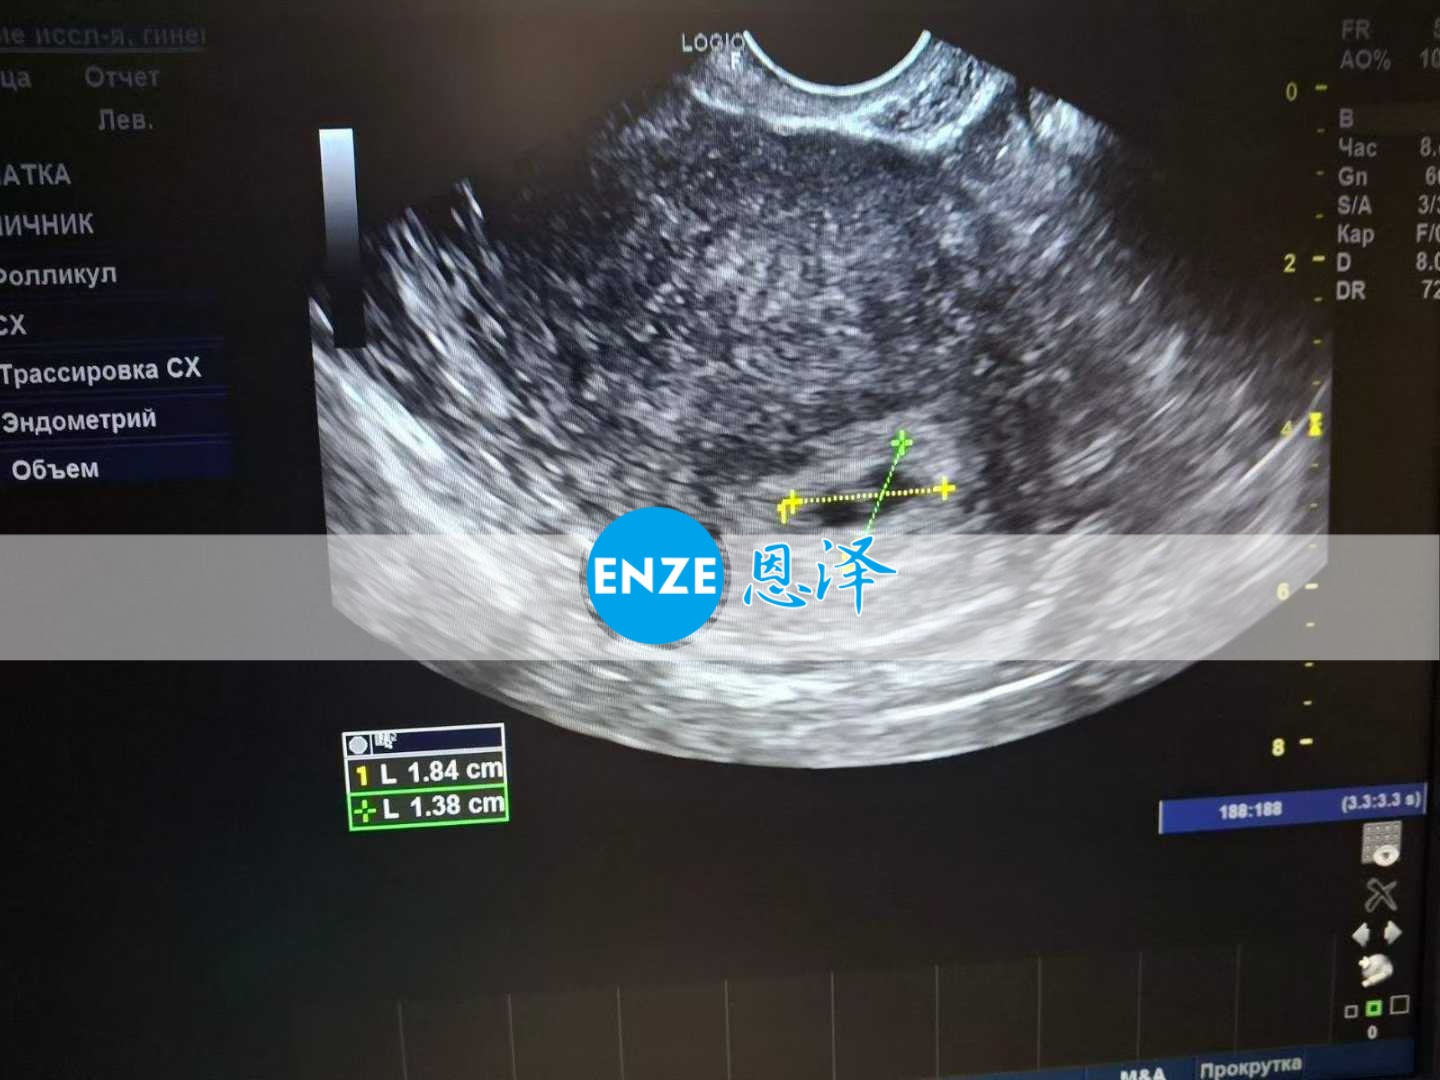

恩泽乌克兰代孕代母34周检查顺利通过

恩泽乌克兰爱缘好孕代孕代母9月17日34周检查顺利通过,还有一个多月到站。